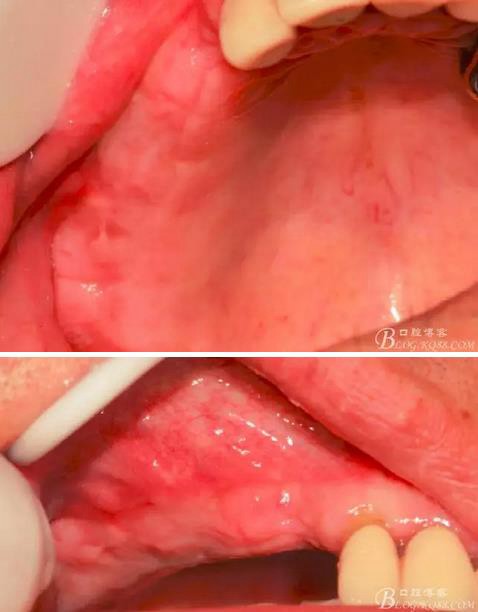

術(shù)后10天口內(nèi)照。

術(shù)后40天口內(nèi)照。